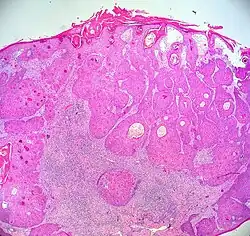

A microscopic examination of the swab test that is taken from the walls of the pharynx will reveal thickened, keratinized, squamous epithelium[4] and may appear lobulated pedunculate. The sizes may vary from small to large. A larger growth or an accumulation of small growth can determine how a person may feel since any growth can be uncomfortable in the back of the throat. This is determined to be one of the main contributions of this condition.